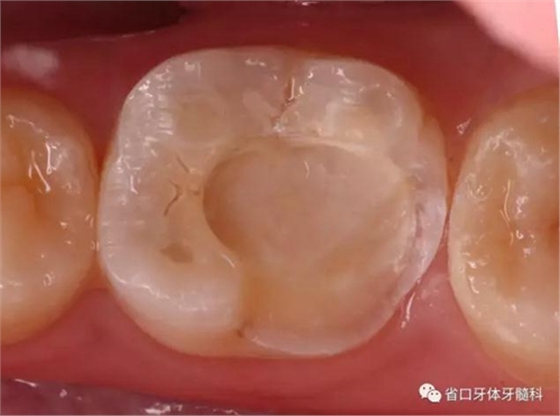

圖6 嵌體預備后

圖7 嵌體粘接后